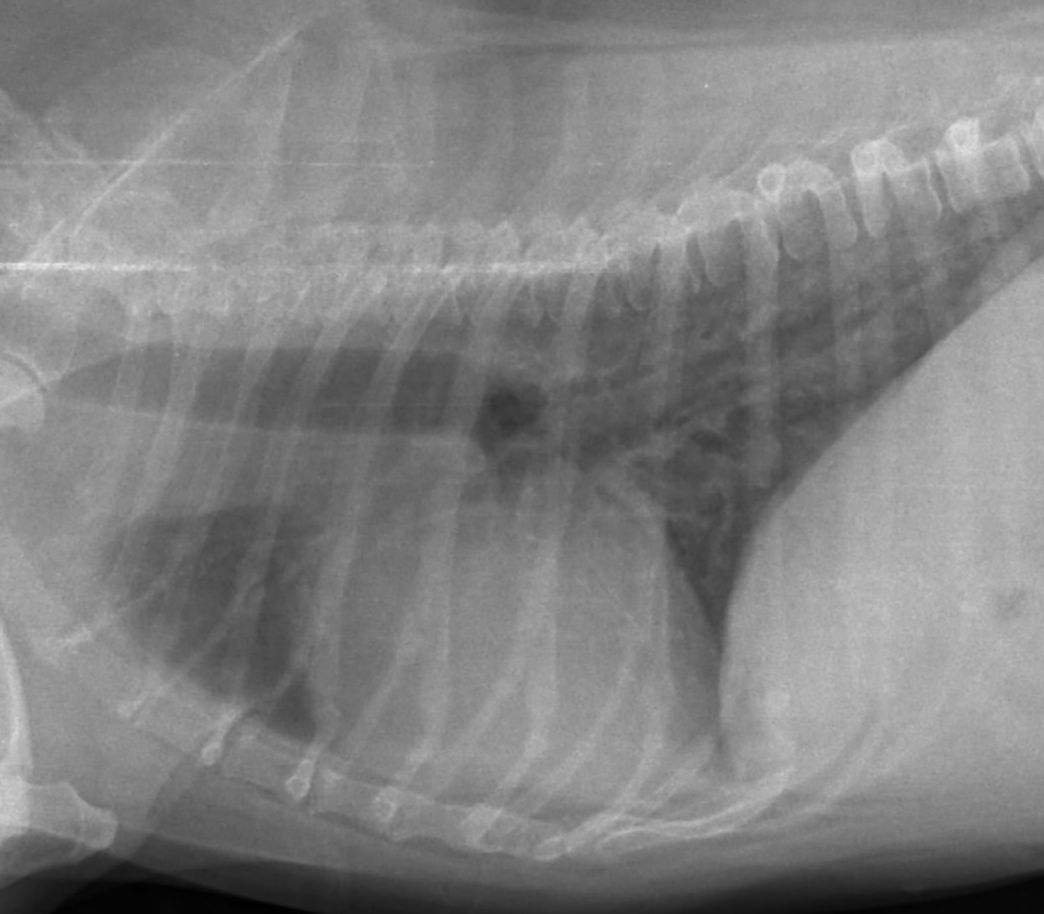

2. Witam mam dość ciężki przypadek mam psa(kundla) ok 15 kilo wiek 17 lat. pies ma chęci do życia i apetyt ale krztuszenie się ciągłe nie pozwala mu już żyć. byłem u weterynarza robilismy usg wskazło ze ma juz powiekszone serce wątrobę no wiadomo nie jest młody.pies przestaje się krztusić jak idzie na spacer jedynie. w nocy juz spac nie daje bo słychac jak sie krztusi. odksztusza płyn czasem typu ślina. dostaje tabletki:CARDISURE 10 MG ćwiartkę dziennieTheospirex retard 150mg pół tabletki dziennieacticor 5mg pół tabletki dzienniefurosemid 40 mg całą dziennie sytuacja się pogarsza. czuja że sie udusi lada dzień. weterynarz mówił ze zapadła mu sie tchawica tez prawdopodobnie juz i dlatego się tak krztusi pytanie czy mogę coś jednak jeszcze zrobić.. inne tabletki.. więcej tabletek operacje. odessać nadmiar płynu ,, nie wiem cokolwiek.. proszę o pomocwstawiłem filmik nagrany podczas krztuszenia może coś pomoże.www.youtube.com/watch?v=l3x8DEqfMWY